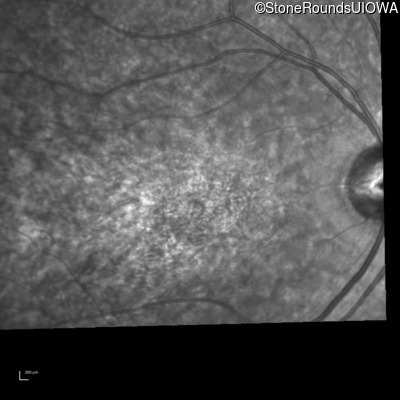

Infrared Fundus Photograph - Left - 20/60

Exemplar